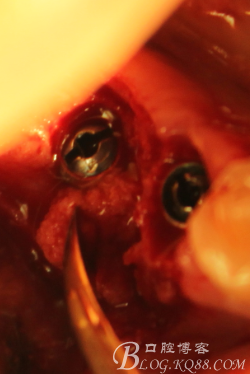

植入植體

C6頰側(cè)填入自體骨,嚴(yán)密縫合關(guān)閉創(chuàng)口

三維檢查種植體位置,方向,平行度